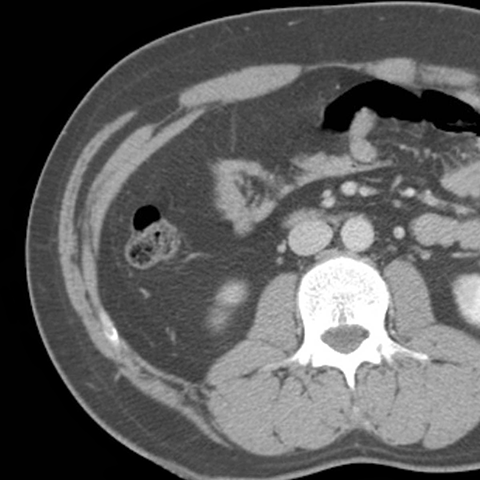

Abdominal Wall Muscles Normal Anatomy, Axial CT [4 of 9]